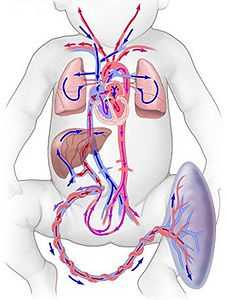

Система маточно-плацентарного кровотока представляет собой анатомически сложный комплекс из плаценты, а также кровеносных сосудов матери и плода.

Уровни маточно-плацентарной системы:

- Основными сосудами, приносящими кровь к плацентарному комплексу, являются конечные ветви маточных артерий. Интересен тот факт, что до беременности эти артерии носят название “спиральных”, так как в их составе есть мышечные клетки, способные сокращаться и закрывать просвет сосуда. Это необходимо во время менструации для того, чтобы быстро прекращалось маточное кровотечение. Но что же происходит во время беременности? Уже начиная с 4-5 недели гестации стенки спиральных артерий подвергаются изменениям, а именно - в них исчезает мышечный слой. Благодаря этим процессам поддерживается полноценный приток крови к плаценте. Доказано, что уже к 16 неделе беременности спиральные артерии полностью трансформируются. Однако, именно по этой причине акушерские кровотечения столь массивные, и их так тяжело остановить, ведь конечные ветви маточных артерий уже не спазмируются.

- Плацента является центральным звеном в маточно-плацентарной системе. Именно здесь и происходят наиболее сложные процессы передачи крови от матери к ребенку. Всем давно известен постулат, что материнская и плодовая кровь не смешиваются. Но как это происходит? Все это достигается благодаря сложному анатомическому строению. Плацента очень прочно прикреплена к внутренней стенке матки при помощи так называемых ворсин. Эти “выросты” плацентарной ткани как бы погружены в толщу слизистой матки. Ворсины плаценты внедряются в стенки маточных сосудов и практически “омываются” материнской кровью. Именно здесь, на клеточном уровне, происходят сложные процессы диффузии материнской и плодовой крови, отделенные друг от друга всего лишь несколькими слоями клеток. Это называется “гематоплацентарным барьером”, что дословно означает “преграда между кровью матери и плацентой”. Кроме того, именно в плаценте “встречаются” два потока крови: от матери к ребенку и наоборот. Такая сложная и хрупкая система не может не вызывать восхищения!

- Сосуды пуповины являются третьим уровнем в сложной системе кровотока между матерью и ребенком. В пуповине содержатся три сосуда: две артерии и одна вена. Гемодинамика (кровообращение) плода устроена таким образом, что артерии приносят кровь к органам и тканям малыша, а вена - наоборот, выполняет функцию обратной передачи крови к плаценте. Нарушение кровотока на данном уровне называют “плодово-плацентарным”, оно является наиболее тяжелым вариантом для плода в плане прогноза.